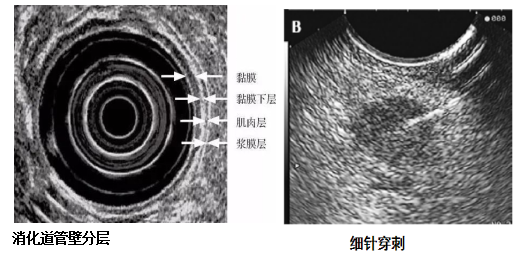

超声内镜(EUS)诊疗技术

消化道超声内镜检查(,EUS)是通过安装在内镜先端或经由内镜插入的超声探头进行实时扫描,可以在内镜观察消化道腔内形态的同时获得消化管壁层次以及周围邻近脏器的声学特征。由于兼具内镜和超声功能,EUS被称为内镜医生的第三只眼。

EUS可开展项目:1.对消化道肿瘤进行术前分期;2.对粘膜下肿物判断性质及来源;3.对消化道周围脏器及组织进行超声检查,比如后纵隔疾病、胆胰疾病、盆腔疾病、肝左叶疾病等;4.对EUS探及病变进行病理穿刺细胞学或组织学检查;5.对EUS探及病变进行注药治疗。